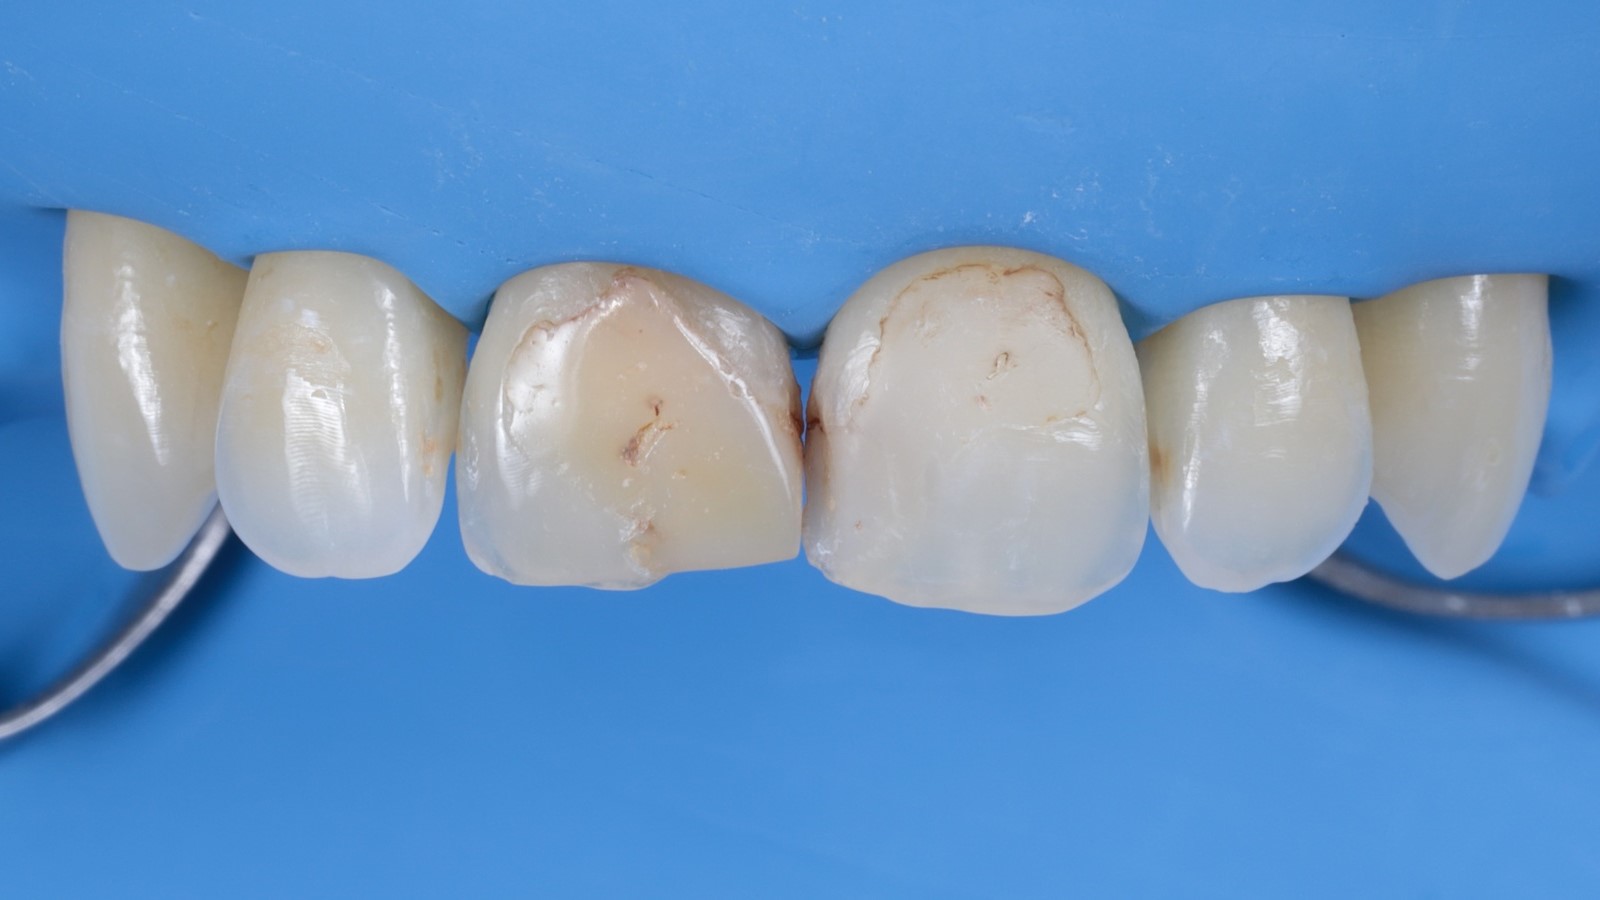

The patient presented with insufficient composite fillings on tooth 11 and 21. The goal was to restore the central incisors with a single shade to achieve a natural, aesthetic appearance.

The old composite and any decayed tissue was carefully removed to prepare the teeth for the new restoration.